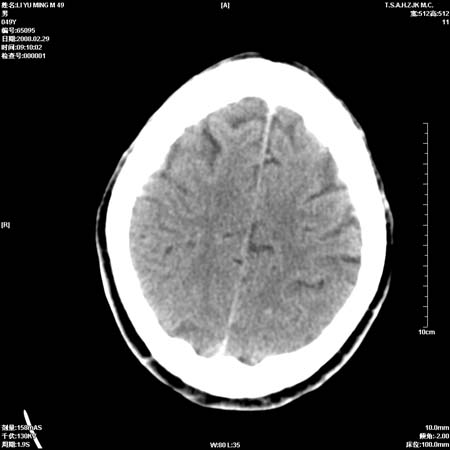

男性, 49岁, 头痛, 行ct检查后, 我科一名大夫报了蛛网膜下腔出血, 请大家讨论!

大脑纵裂池及鞍上池应该有蛛血

支持蛛网膜下腔出血。

支持蛛网膜下腔出血

正常

可能为正常。间隔一周蛛血应基本吸收;再过一周复还是这样应该可以肯定了。

一周时间密度未见改变,考虑为正常图像(脑动脉硬化?)。

蛛血可能,建议短期内复查。